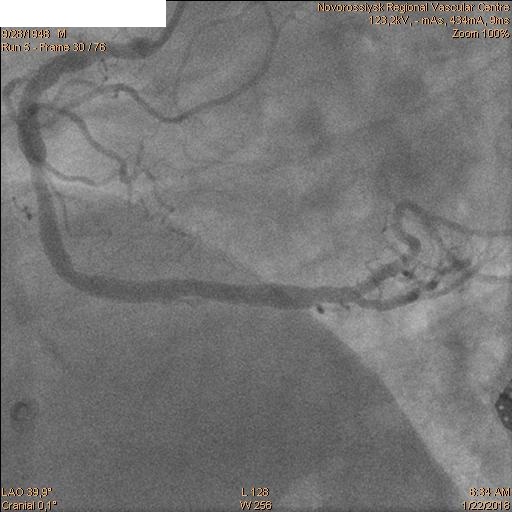

В 06.00 пациент в экстренном порядке подан в рентгеноперационную. Пациенту выполнена коронарография, по данным которой выявлены стеноз ствола ЛКА 60% с переходом на устья ПНА и ОА, окклюзия ПНА от устья и стеноз устья ОА 60%.

После которой было принято решение о выполнении бифуркационного стентирования ствола ЛКА.

Последовательно заведены коронарные проводники в дистальные сегменты ПНА и ОА. Первым этапом была выполнена реканализация, баллонная ангиопластика ПНА баллоном 2.5х20 мм и стентирование ствола ЛКА с переходом на проксимальный сегмент ПНА стентом 4.0х28 мм.

Затем последовательно перепроведены коронарные проводники в дистальные сегмента ПНА и ОА. Баллоном 2.5х20 мм выполнена предилатация ячеек стента. Далее выполнено стентирование ствола ЛКА с переходом на проксимальный сегмент ОА стентом 4.0х28 мм. Затем баллонами 2.5х20 мм и 2.5х15 мм выполнена «kissing» дилатация ствола ЛКА, устья ПНА и устья ОА с великолепным ангиографическим результатом.